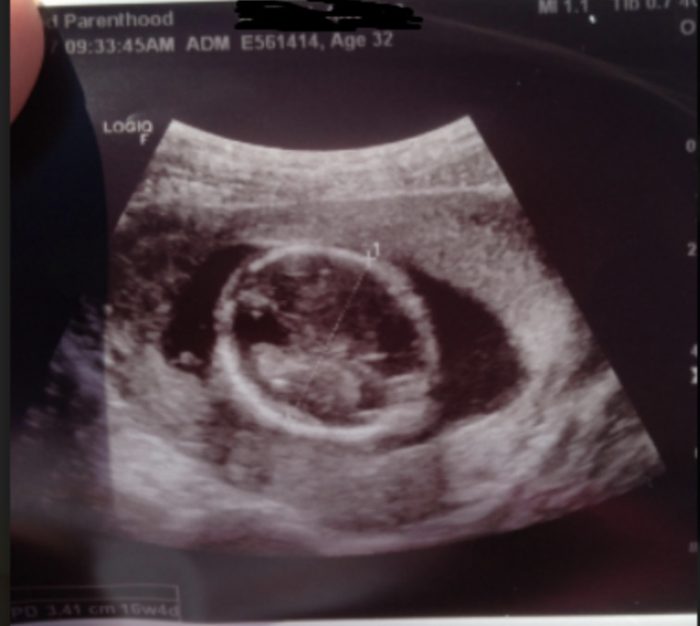

One example from 2017, as previously reported by Live Action News, was of a woman who underwent an abortion in Texas. The law at the time required Planned Parenthood to show her the ultrasound images of her baby, point out the baby’s body parts, such as arms and legs, and allow her to hear the baby’s heartbeat. But when the woman asked to see the ultrasound image, the staff showed her an image of the top of her 16-week baby’s head only — making it appear as if her baby was a mere round blob.

16 weeks 4 days (top of baby’s head only) – Planned Parenthood’s attempt at deceiving patient